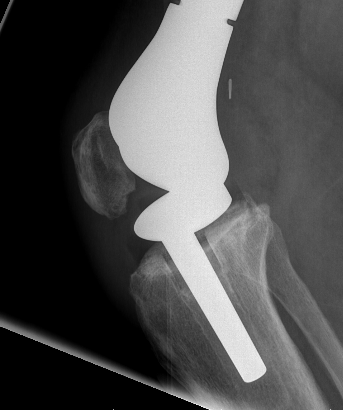

Post distal femoral osteosarcoma resection

Post proximal tibial osteosarcoma resection